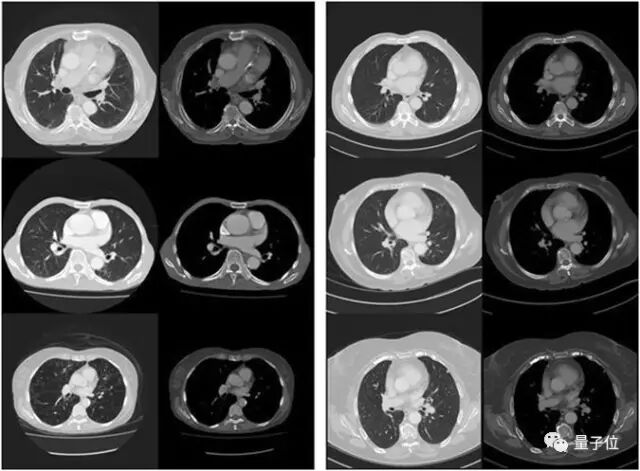

本文来自AI新媒体量子位(QbitAI) 人类,可以在行动之前预想到后果,这是我们认知能力中一种强大的工具。 举例来说,当我们将玻璃杯放在桌子边缘时,我们很可能会考虑一下放得稳不稳,是否会掉下来。基于对后果的思考,我们可能会调整玻璃杯的位置,避免掉在地上打碎。 这种慎重性的思考本质上是“想象力”。这是一种人类独有的能力,也是日常生活中重要的工具。 如果我们希望算法实现同样的复杂行为,那么算法也必须能够“想象”,对未来进行推理。除此以外,算法必须利用这些知识构建计划。 在这个领域,我们已看到了丰富的成果,例如AlphaGo这样的程序。AlphaGo利用“内部模型”,分析每步操作会在未来带来什么样的结果,从而进行推理和计划。 这些内部模型非常强大,因为围棋是一种“完美的”环境。围棋有明确定义的规则,因此在几乎任何情况下都可以非常准确地预测结果。 然